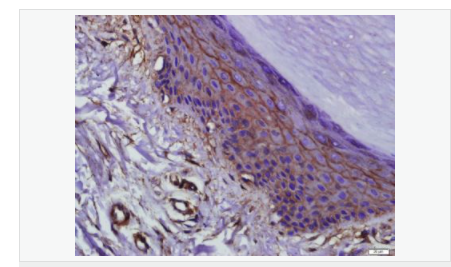

| 產(chǎn)品應用 | WB=1:500-2000 ELISA=1:5000-10000 IHC-P=1:100-500 IHC-F=1:100-500 Flow-Cyt=1μg/Test ICC=1:100 IF=1:100-500 (石蠟切片需做抗原修復) not yet tested in other applications. optimal dilutions/concentrations should be determined by the end user. |

| 產(chǎn)品介紹 | This gene encodes an integral membrane protein which is located at tight junctions. This protein may be involved in the formation and maintenance of the tight junction. The possibility of several alternatively spliced products has been suggested but the full nature of these products has not been described. [provided by RefSeq]. Function: May play a role in the formation and regulation of the tight junction (TJ) paracellular permeability barrier. Subunit: Interacts with TJP1/ZO1 and with VAPA. Subcellular Location: Membrane; Multi-pass membrane protein. Cell junction, tight junction. Tissue Specificity: Localized at tight junctions of both epithelial and endothelial cells. Highly expressed in kidney. Not detected in testis. Post-translational modifications: Phosphorylated upon DNA damage, probably by ATM or ATR. Dephosphorylated by PTPRJ. May be phosphorylated by PKC during translocation to cell-cell contacts. Similarity: Belongs to the ELL/occludin family. Contains 1 MARVEL domain. SWISS: Q16625 Gene ID: 100506658 Database links: Entrez Gene: 18260 Mouse Entrez Gene: 100506658 Human Omim: 602876 Human SwissProt: Q16625 Human SwissProt: Q61146 Mouse Unigene: 592605 Human Unigene: 4807 Mouse Unigene: 31429 Rat Important Note: This product as supplied is intended for research use only, not for use in human, therapeutic or diagnostic applications. |